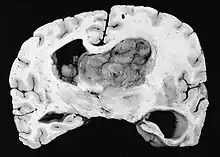

a,b)Images of subependymal giant cell astrocytomas arrowheads

MRI of brain with sub-ependymal giant cell astrocytoma

Diagnosis is made by imaging with a contrast-enhanced MRI or CT scan of the brain.[3]